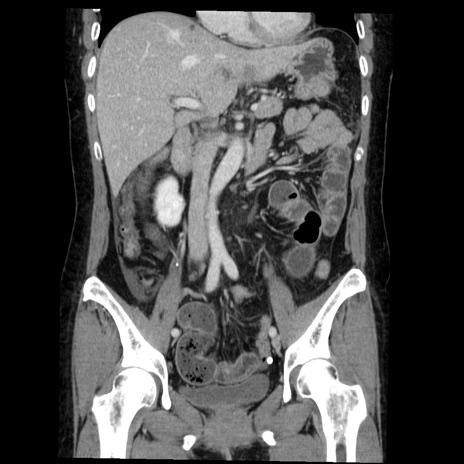

症例6(冠状断像)

【症例】50歳代女性

【主訴】下腹部痛

【現病歴】本日朝より下痢2回あり。 昼食を食べた後、嘔吐3回、下腹部痛認め、症状軽快せず、当院救急搬送。

最終食事:本日昼(生ものなし)。 昨日の夜、刺身を食ぺたとのこと。周囲に同様の症状の者なし。普段、排便は毎日あるとのこと。

【既往歴】卵巣癌術後(8年前に当院で卵巣摘出)

【身体所見】 意識清明、腹部:平坦、腸蠕動音→、やや硬、下腹部自発痛・圧痛あり、反跳痛あり、筋性防御なし。

【データ】WBC 16000、CRP 0.01